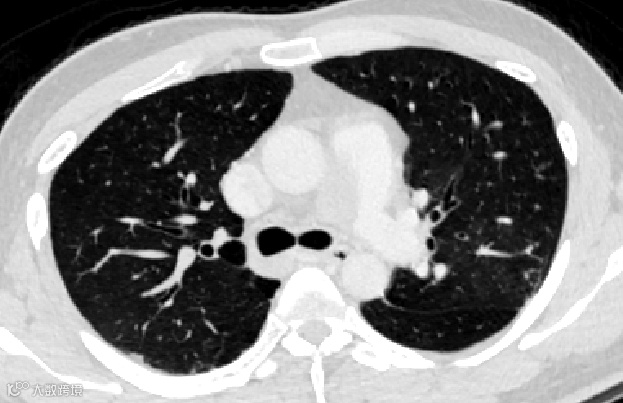

经ct评估,发现患者双肺多发肺动脉栓塞,右肺动脉干远端血栓形成并钙化、主肺动脉稍增宽、右心房血栓形成并钙化可能。针对患者情况,专家们进行多学科会诊,认为该患者情况复杂,建议实施开胸手术取出栓塞物。

考虑患者情况特殊,血栓分布较广,血管外科团队术前采用思源智慧医疗3D打印模型,观察血栓的分布情况,对手术进行规划。降低了手术时间,减少了手术风险,最终手术圆满成功!家属激动地说:“是厦心医院给了他第二次生命”。